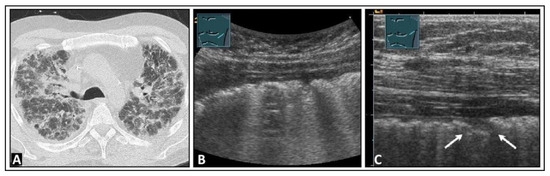

6. Interstitial Lung Disease

7. Other Pathologic Situations